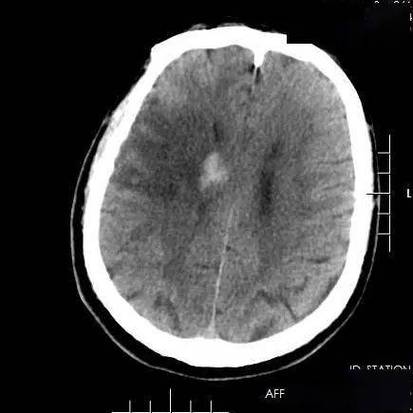

(图片来源网络,侵删)

- 寻找危险因素:医生会为您安排一系列检查,来找出导致脑梗的根本原因和危险因素,这些检查通常包括:

- 血液检查:血糖、糖化血红蛋白(看糖尿病情况)、血脂(总胆固醇、甘油三酯、低密度脂蛋白LDL-C)、同型半胱氨酸等。

- 心脏检查:心电图、24小时动态心电图,甚至心脏超声,以排查房颤等心脏问题。

- 血管检查:颈部血管超声(看颈动脉有无斑块)、经颅多普勒超声(TCD,看颅内血管情况),必要时可能做CTA或MRA(血管造影)来更详细地评估脑血管状况。